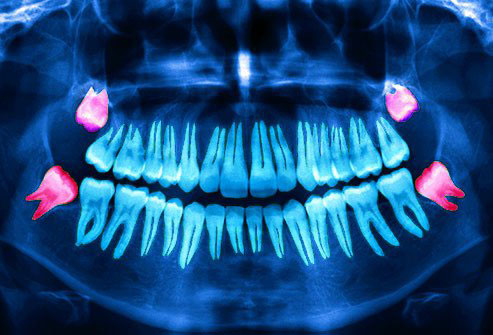

Wisdom teeth generally erupt into the mouth by the age of 18 years and may even extend upto 22 years or even later. They may erupt into the oral cavity depending on the space available or may remain in the bone unerupted. Their eruption into the oral cavity depends on many factors like the space available, the position of the tooth, early shedding of the other teeth.

Here in SACHIN DENTAL CLINIC, the whole procedure is done in a highly sterilized environment. Prior to the removal, an X-Ray evaluation and the possible complications are discussed with the patient.